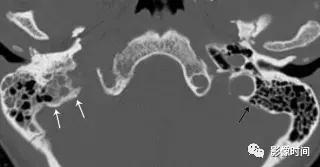

(2).颈静脉球瘤:可发生于舌咽神经鼓室支或迷走神经耳支,50-60 岁男性多见,临床症状多为耳鸣、听力损失或眩晕,和其他与颈静脉孔内的颅神经有关的症状。

模式图显示颈静脉球瘤富含血管,包绕颅神经伴「虫噬状骨质破坏」。CT 显示颈静脉孔区「蛀虫」的骨质破坏。增强 MRI 显示颈静脉孔区增强肿块 (白色箭头),注意流空信号 (黑色箭头)。